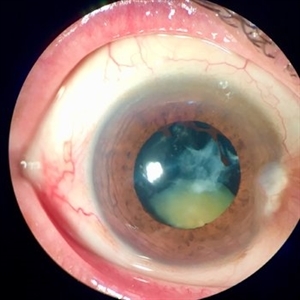

Lens Bite

May 30 2016 by Andrea Arriola-Lopez, MD MSc

32-year-old man underwent a vitrectomy due hemovitreous. There was a dense retrolental membrane, while aspirating it, a little bite to lens was done. We decided not to performed lensectomy. VA is 20/30 two months later.

Photographer: Andrea E. Arriola-López MD MSc

Condition/keywords: lens, lens opacity